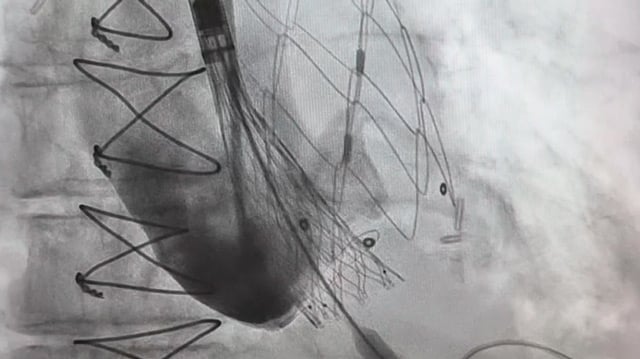

A challenging valve-in-valve scenario in a patient with prior aortic coarctation repair

A 79-year-old with a degenerated aortic bioprosthesis after complex coarctation surgery challenges conventional strategies. Which access route would you choose?